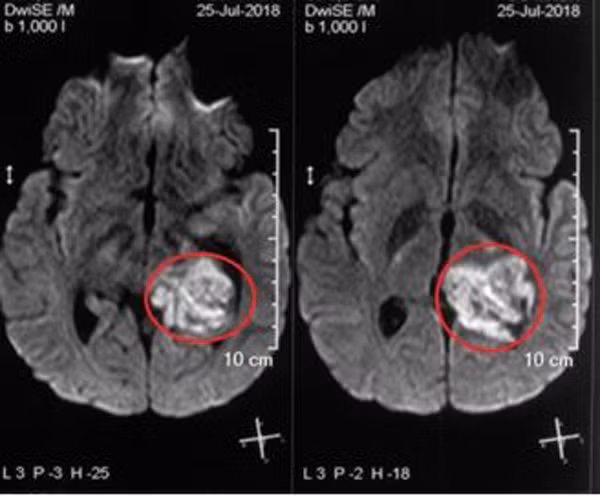

| Hình ảnh khối u ở não bệnh nhân |

Tuy nhiên nam thanh niên vẫn khoẻ mạnh, không hề bị liệt chi, không sốt, không rối loạn đại tiểu tiện, không đau bụng. Khi vào BV đa khoa tỉnh Nghệ An chụp cộng hưởng từ sọ não, bác sĩ phát hiện khối u lớn ở hồi hải mã trái. Sau đó BV tỉnh đã chuyển bệnh nhân ra Trung tâm Y học hạt nhân và Ung bướu, BV Bạch Mai để điều trị tiếp.

Khi vào viện, bệnh nhân được X-quang tim phổi, siêu âm ổ bụng nhưng không thấy bất thường. Chụp cộng hưởng từ sọ não có hình ảnh khối u lớn hồi hải mã trái kích thước 2,9×3,9cm, là u thần kinh đệm ít nhánh, giai đoạn 3.